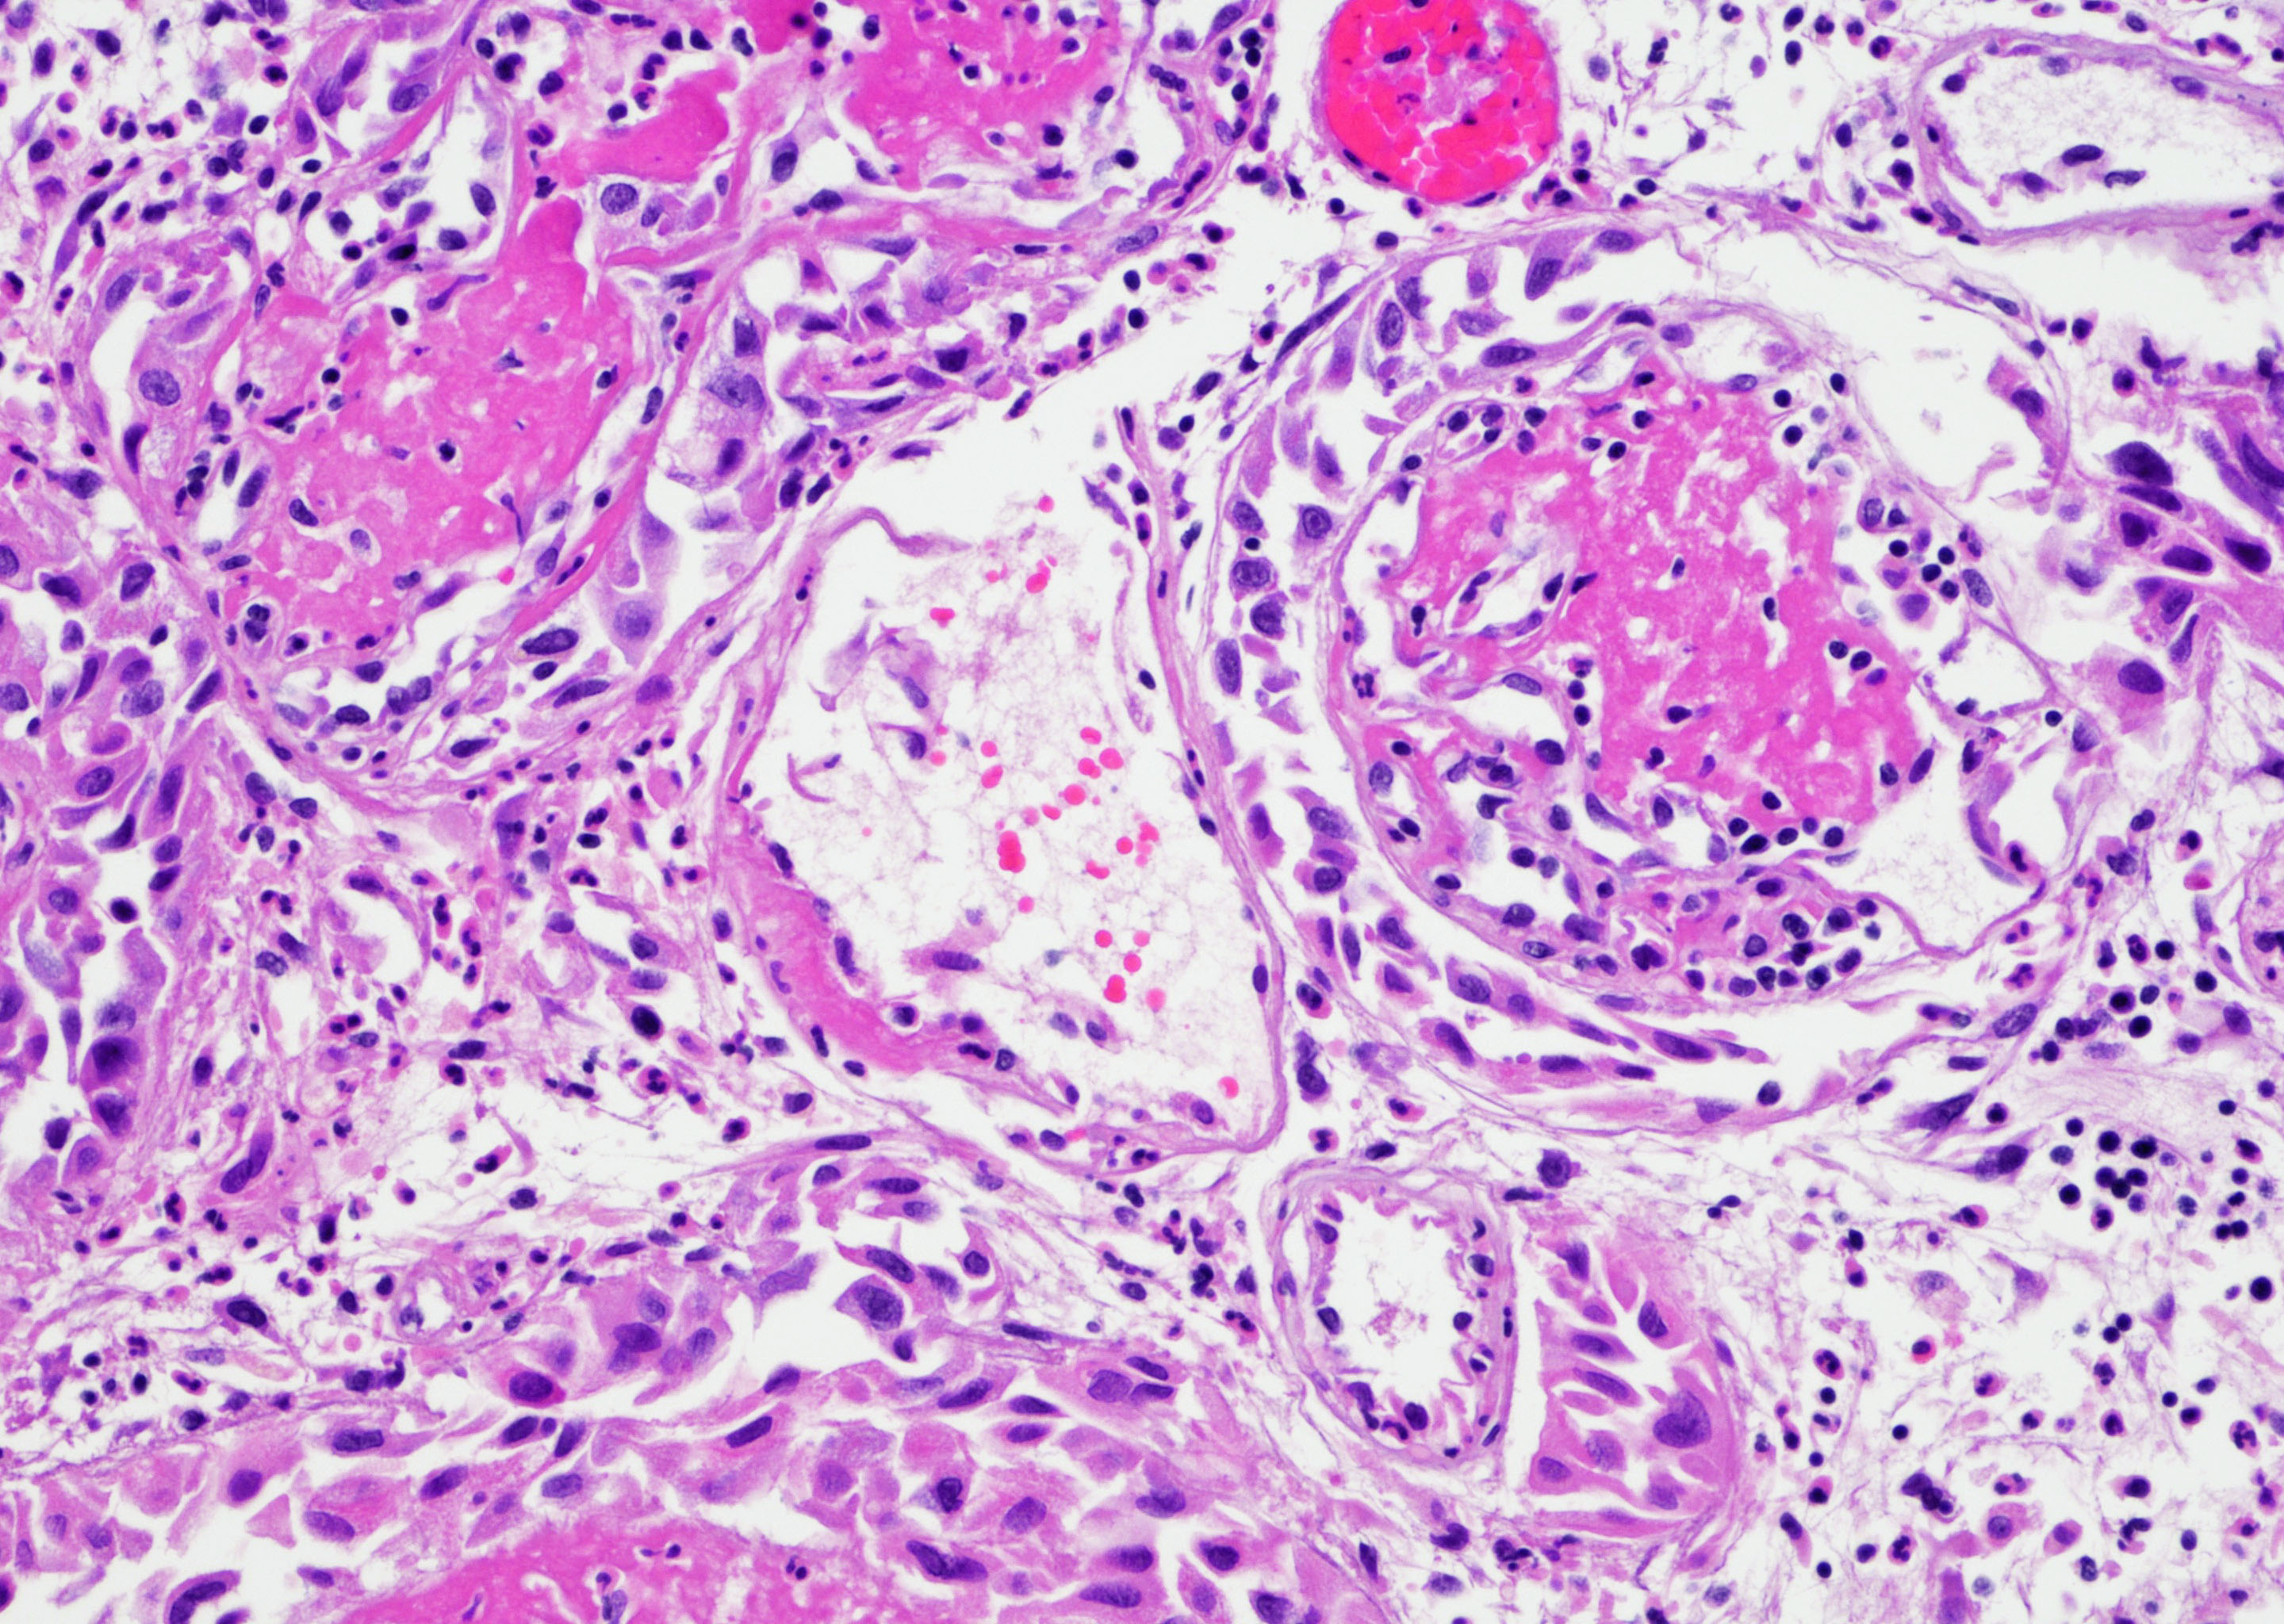

- Vessels with fibrin thrombi, fibrinoid vascular necrosis, vascular congestion, thickened walls, endothelial proliferation and telangiectasia

- Acute and chronic inflammation

- Reactive multinucleated stromal fibroblasts with smudgy nuclei

- Fibrosis and edema

- Hemorrhage and hemosiderin

- Pseudocarcinomatous urothelial hyperplasia: variable sized urothelial cords and nests with rounded or irregular edges present in the lamina propria and enclose dilated blood vessels with fibrin deposition (Am J Surg Pathol 2008;32:92)

- Acute phase: edematous, congested and telangiectatic vessels, acute and chronic inflammatory infiltrate, atypical stromal cells with multinucleated forms

- Chronic phase: atrophic urothelium, atrophic smooth muscle layer, collagen deposition (fibrosis) (Am J Surg Pathol 2004;28:909)

Microscopic (histologic) images

Contributed by Y. Albert Yeh, M.D., Ph.D. and Jennifer Lee, M.D.

- Comment: There is a history of radiation therapy per the medical record. The transurethral resection of the bladder lesion shows fragments of urothelial mucosa with total and partial denudation of urothelium. The urothelial lining cells show reactive changes. There is marked edema, hemorrhage and mixed inflammatory infiltrate composed predominantly of neutrophils and lymphocytes in the lamina propria. Reactive multinucleated stromal fibroblasts are seen. Telangiectatic vessels with fibrinoid necrosis and intravascular fibrin deposition are seen. Anastomosing cords and nests of urothelial cells encircling the vessels with fibrin deposition is evident. Urothelial cells with hyperchromatic nuclei, increased nuclear to cytoplasmic ratio and prominent nucleoli are seen. These features are consistent with radiation cystitis with pseudocarcinomatous urothelial hyperplasia. Muscularis propria is not identified in this specimen.

A 68 year old man presented with hematuria and dysuria. He has a medical history of prostate cancer that was treated with radiation therapy. Cystoscopy revealed hemorrhage in the right bladder wall. A transurethral resection of the lesion was performed. A photomicrograph is shown above. What is the diagnosis?

- Radiation cystitis with pseudocarcinomatous hyperplasia

C. Radiation cystitis with pseudocarcinomatous hyperplasia. Answers A, B and D are incorrect because anastomosing cords and nests of urothelial cells encircling ectatic vessels with intravascular and stromal fibrin deposition in a background of mixed inflammation are not present in these entities.